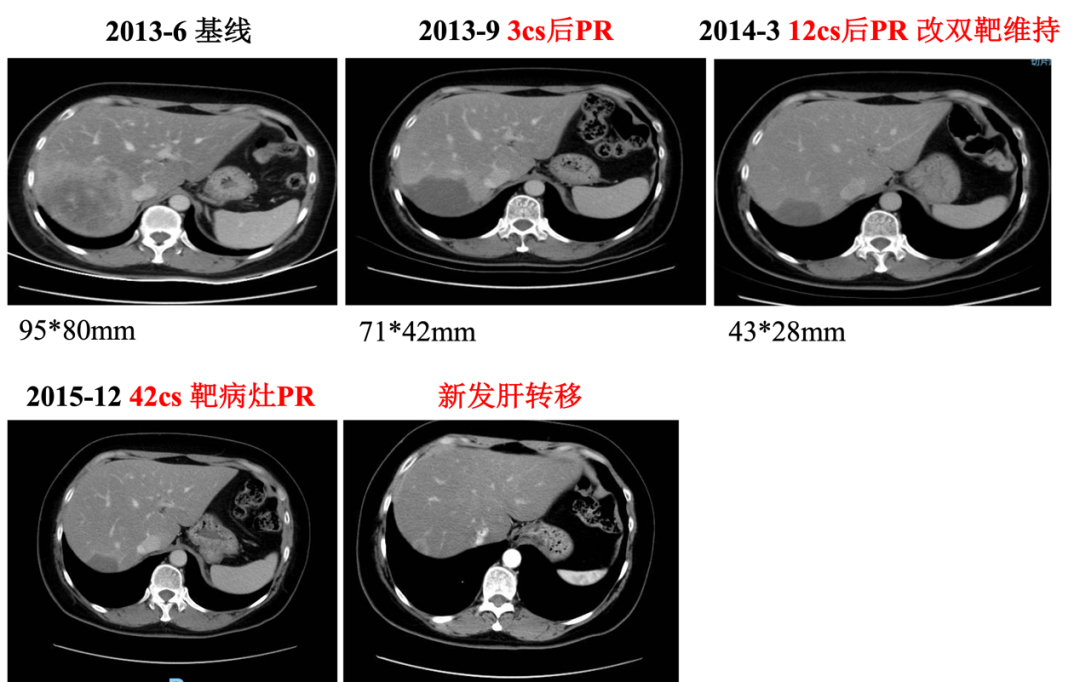

▌一线治疗:

入组MO28047临床试验(PERUSE研究),于2013-7-16开始行紫杉醇+曲妥珠单抗+帕妥珠单抗方案治疗,具体:紫杉醇175mg/m2 270mg d1;帕妥珠单抗首剂840mg,以后420mg d1;曲妥珠单抗首剂 8mg/kg 484mg,以后6mg/kg 363mg d1,Q21d。最佳疗效PR,自第10周期调整为双靶维持治疗。2015年12月(42周期时)原靶病灶维持PR,新发18mm肝转移,评效病情进展,PFS为30月。不良反应:腹泻2级,粒细胞下降2级。

图2. 一线治疗